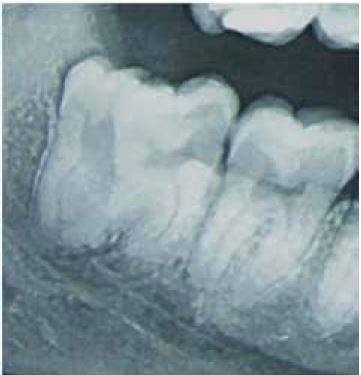

Al examen radiográfico se observa la fusión de dos piezas dentarias (tercera y cuarta molar) en posición vertical; no existe un espacio interdental entre ambas piezas dentarias, la pieza fusionada presenta dos raíces, una de ellas de la tercera molar y la otra raíz presenta fusión: la raíz distal de la tercera molar con la raíz de la cuarta molar. Según Winter la posición es vertical y según Pell y Gregory es clase 3 posiciones A; siendo así el diagnóstico definitivo tercera molar fusionada a cuarta molar retenida en posición vertical (figura 2).